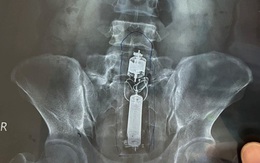

Cụ ông nhập viện với quả đạn pháo trong... trực tràng

Lực lượng tháo gỡ bom mìn được huy động, bệnh viện buộc phải sơ tán giữa đêm khi một cụ ông xuất hiện với một quả đạn pháo trong trực tràng. Một quả đạn pháo khá là... ố dề luôn đó bà con?!